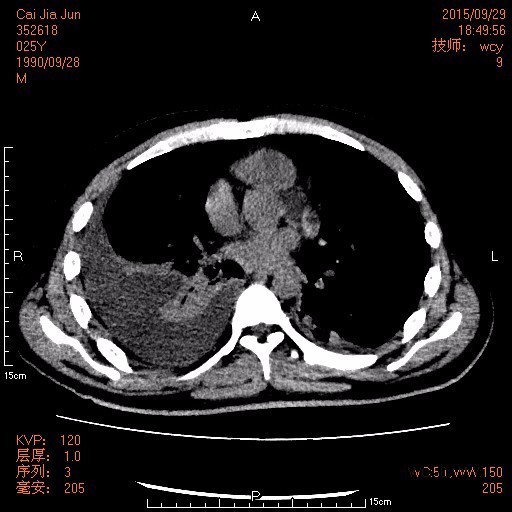

查体: 腹部平软,右下腹及右上腹可见两条引流管,引流出棕色臭味脓液,右下腹有压痛、反跳痛,余腹无压痛及反跳痛。 辅查: 1.腹部CT:1.原阑尾炎穿孔并周围及腹盆腔多发包裹性脓肿形成治疗后复查,现累及范围如上述,与前对比盆腹腔多发脓肿明显吸收变小。 2.腹膜炎;腹腔少量积液,与前对比减少。 3.双侧胸腔积液,与前对比减少;双肺下叶节段性肺不张,较前复张。 4.肝多发小囊肿。 2.胸片:1.右侧胸腔中量积液,左侧胸腔少量积液。 2.双下肺炎症及肺压缩性不张。 3.腹腔引流液培养:大肠埃希菌;屎肠球菌(D群)。

诊断:阑尾穿孔并腹腔脓肿形成。 治疗:伤口换药、抗感染、补白蛋白、控制血糖等处理,复查CT见腹腔包裹性脓肿明显吸收变小,予拔除引流管,无明显发热,予办理出院。